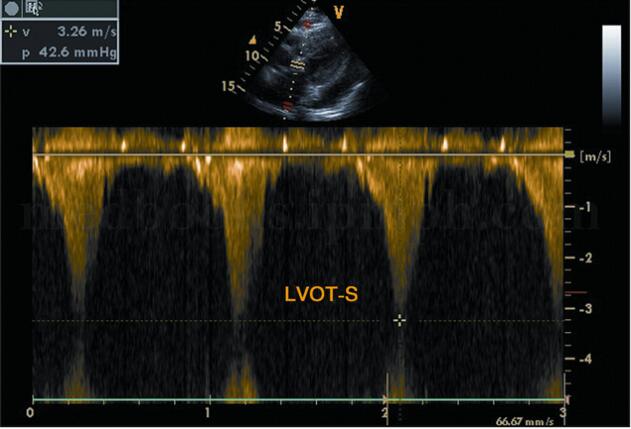

超声图片 如图2‐1‐196,图2‐1‐197。

超声描述 左房轻度增大,室间隔呈团块状明显增厚(39.7mm),左室后壁轻度增厚(11.4mm),两者之比>1.5∶1,呈非对称性;室间隔回声增粗明显不均,呈毛玻璃样改变;二尖瓣水平M型见二尖瓣前叶EF斜率下降,E峰与室间隔相碰,SAM现象(+);左室流出道狭窄,其内收缩期充满花彩血流束,射流流速3.56m/s,压差50.7mmHg。

超声诊断 肥厚型梗阻性心肌病。

(2)梗阻者:左室流出道频谱为负向高速充填状射流。形态为上升支曲线逐渐上升,收缩晚期达高峰,呈“匕首”样(图2‐1‐210)。左室流出道内压力阶差>30mmHg时提示有梗阻。